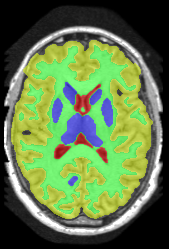

![]() |

|

Subject 3 |

Subject 4 |

| ground truth | a-exp [7, 8] | QPBO [25, 8] | ours | |

Brain Segmentation:

We combined the labeled regions in dataset [19] (T1W MRI) to create the tree shown in Fig. 15(a). In this setting, the data term is the sum of color model penalty and an shape prior [5] based on an automatically extracted brain mask using [16],

where is the intensity at pixel and is the Euclidean Distance Transform of the extracted brain mask. Min-margins are shown in Fig. 15(a). We also added a Hedgehog prior [13] for the sub-cortical grey-matter to help our energy differentiate between grey-matter and sub-cortical grey-matter.

In this application our method outperformed QPBO in most cases and a-exp in all cases. In fact a-exp always converged to a weak local minima in this setting, see Fig. 15. Based on our experience the quality of a-exp result depends on various factors, e.g. tree complexity, the number of min-margins introduced, the order in which labels are expanded, and the initial solution. For the subjects that QPBO was able to find the global optimal Path-Moves either found the global optimal or a very close solution.